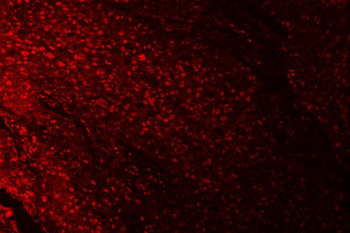

IF analysis of RPRD1B using anti-RPRD1B antibody. RPRD1B was detected in a paraffin-embedded section of human esophageal squamous cell carcinoma tissue. Heat mediated antigen retrieval was performed in EDTA buffer (pH8.0, epitope retrieval solution). The tissue section was blocked with 10% goat serum. The tissue section was then incubated with 5 µg/mL rabbit anti-RPRD1B Antibody overnight at 4°C. DyLight®550 Conjugated Goat Anti-Rabbit IgG was used as secondary antibody at 1:500 dilution and incubated for 30 minutes at 37°C. Visualize using a fluorescence microscope and filter sets appropriate for the label used.